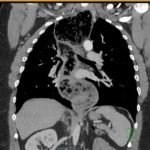

The chest X-ray demonstrated a markedly widened mediastinum (red brackets), raising concern for thoracic aortic aneurysm/aortic dissection, which prompted labs and contrast-enhanced computed tomography (CT) of the chest. The CT revealed a dilated proximal esophagus that narrowed distally (yellow tracing and red arrow), with particulate material, mass-effect on the trachea (purple outline), and bilateral patchy opacities suggesting aspiration. Barium esophagram showed a drastically dilated esophagus filled with contrast (yellow arrow), terminating into the classic “bird’s beak sign” (red arrow) at the lower esophageal sphincter (LES). Esophageal manometry later confirmed achalasia, proving that widened mediastina can have unexpected etiologies.